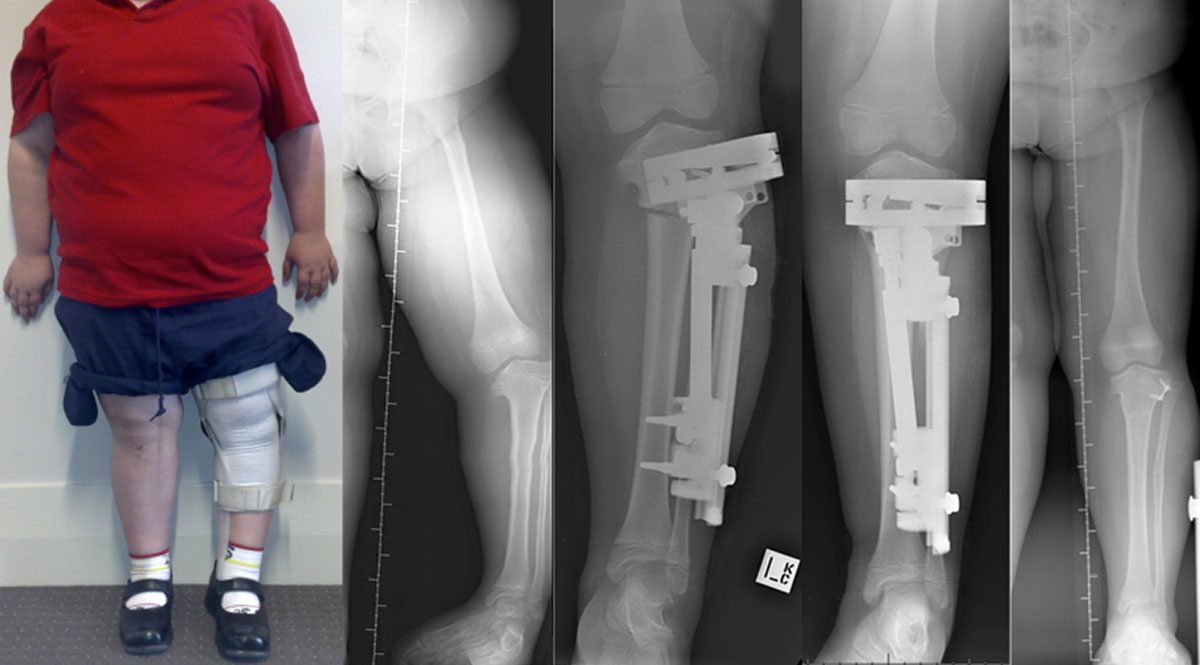

Dr. Vikram Veer

हड्ड़ी, जोड़, लकवा, गठिया ( पोलियो ) नस, स्पाइन, विशेषज्ञ सर्जन

Fello Rheumatology from John Hoppins University (USA)

M.B.B.S.,M.S, D.Ortho., F.I.M.s.(USA) M.Ch.(Ortho) Ex. S.O.D. Dept. of Orthopaedics, P.M.C.H., Patna Ex. Consultant, Kurji Holy Family Hospital, PatnaHappy Patients